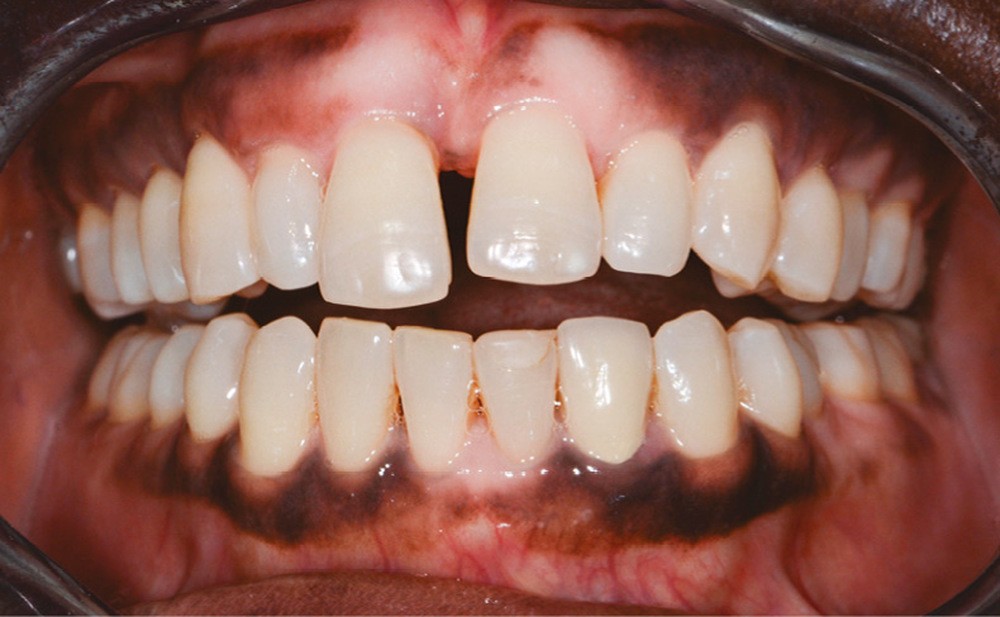

Une femme âgée de 33 ans, sans antécédents médico-chirurgicaux notables, consulte pour la correction de l’égression de son incisive centrale qu’elle juge disgracieuse dans le sourire (fig. 1).

À l’examen clinique et radiologique, elle présente une parodontite de stade 4 grade C avec des poches profondes au niveau des dents 11 et 24, associées à des alvéolyses angulaires atteignant la moitié ou les deux tiers de la hauteur radiculaire au niveau du secteur incisivo-canin maxillaire, et le quart de la longueur radiculaire des premières molaires maxillaires et mandibulaires (fig. 2).

L’observation clinique après traitement parodontal initial révèle, au niveau interarcade, des rapports de classe I molaire bilatéraux associés à des rapports de bout à bout incisif. Dans la dimension verticale, elle présente une légère infraclusion antérieure. On ne note pas d’anomalie de la dimension transversale (fig. 3 à 5). À l’examen intra-arcade, on constate des diastèmes maxillaires interincisifs (1 mm), en distal de 13 (0,5 mm) et de 24 (1 mm) ainsi que des malpositions unitaires (linguoversion de 12, rotation mésio-vestibulaire disto-linguale de 24). À la mandibule, on observe une couronne céramométallique au niveau de 32 plus large de 1,5 mm que les autres incisives ainsi qu’une rotation mésio- linguale de 35 (fig. 6 à 8). En diduction, on note une interférence au niveau de 24.